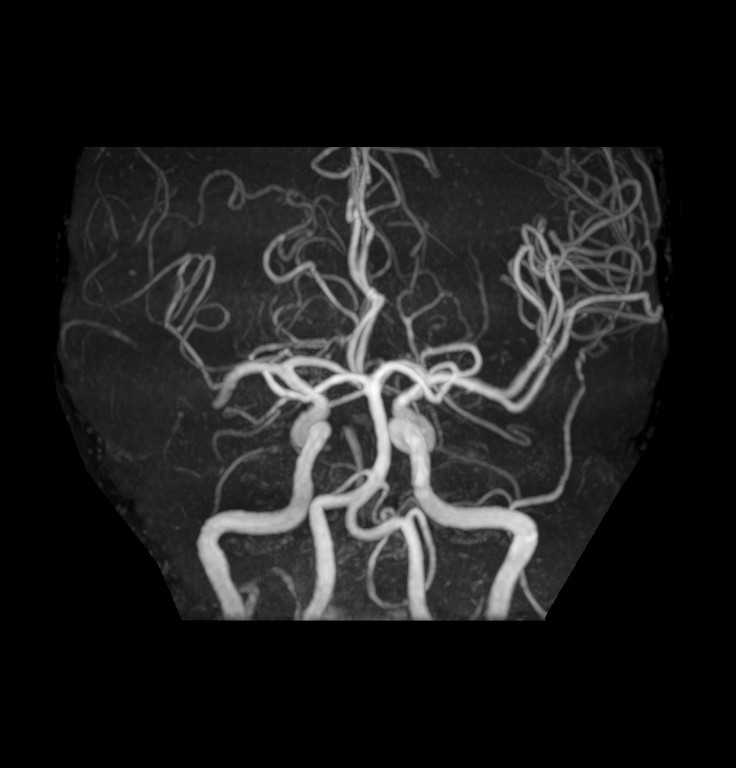

1. 頭部MR検査

頭部の検査では、頭部、特に脳を中心としたMRI検査です。脳実質、腫瘍の有無、脳梗塞の有無、脳出血の有無などの病変の有無を調べることが可能です。